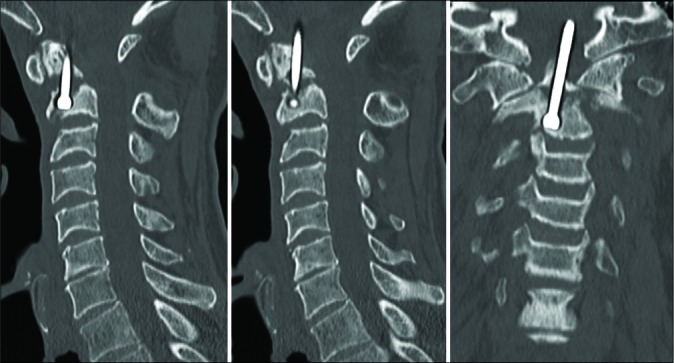

Figure 4:

Sagittal and coronal computed tomography images of the cervical spine 7 months after anterior odontoid screw fixation demonstrating upward migration of the patient’s odontoid screw.